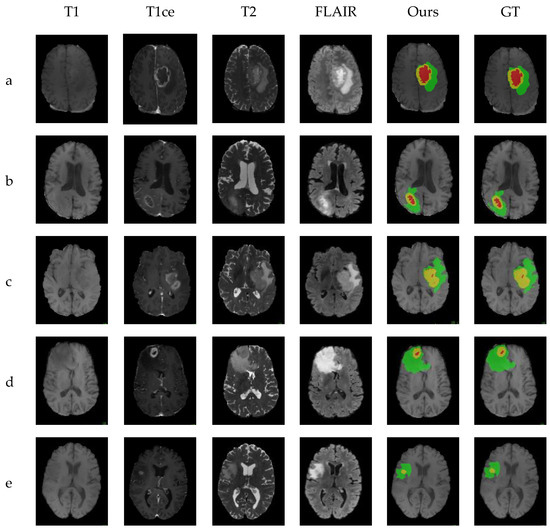

4.4. Comparison with Other Methods